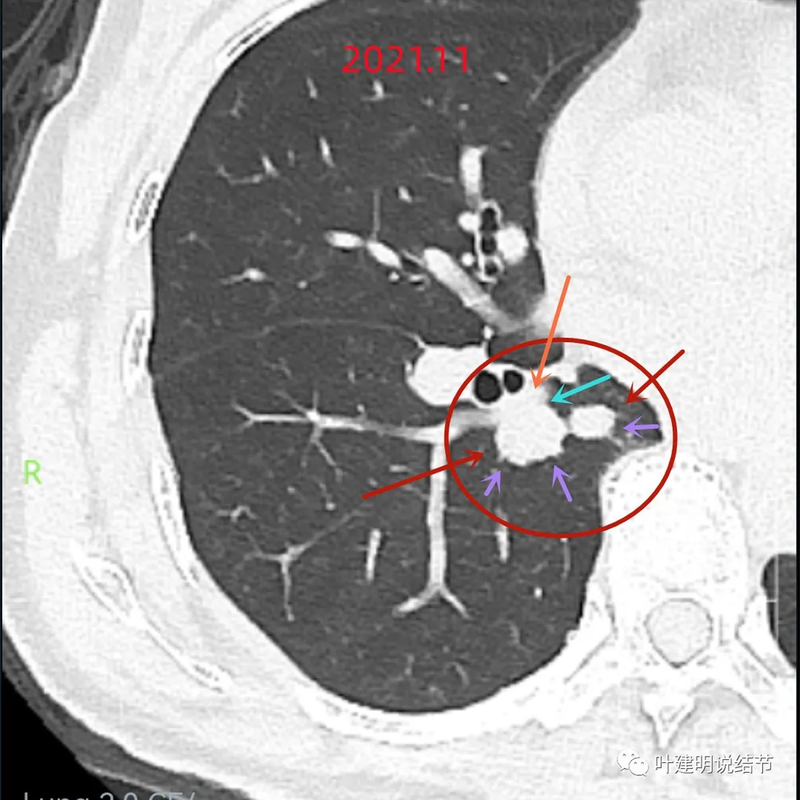

天蓝色箭头示病灶与支气管之间有缝隙,但贴的较近;黄色箭头示支气管管腔;红色箭头示病灶,边缘光滑。

支气管受压,但无明显破坏;与支气管之间紧贴位有的位置仍有缝隙;病灶边缘光滑。

病灶密度较为均匀,对支气管是压迫后移位。表面光滑。

似乎有血管穿过。

边缘光滑,没有毛刺,膨胀性生长。

表面光滑,内部密度较均匀,边界清楚,膨胀性长。

没有侵犯邻近支气管。

边缘光滑,分叶不明显。

上图这个层面感觉病灶与肺血管之间没有明显间隙,似像侵犯或愈着的样子。

结节边缘区域与血管之间又有间隙了的。

下肺静脉水平,病灶基本没有了。